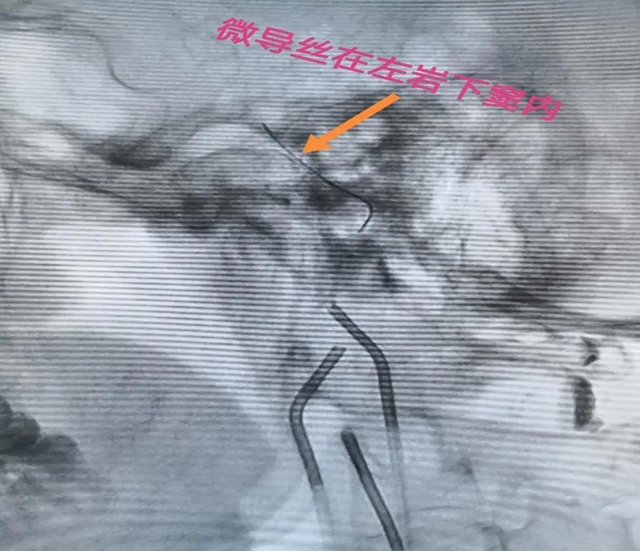

“这项技术需要采血的脑部血管非常细微,对神经介入技术要求很高,但此处采血,最能反应病人实际水平,对定位定性诊断和精准治疗有非常高的临床价值。”黄昌仁教授表示,通过多学科合作完成的这项技术,填补了神经外科神经介入的一项空白,更是多学科联合诊疗的成功范例。

最终,历时两个多小时,采血成功完成。根据取血结果,唐先生确诊患库欣病,再通过比较左右岩下窦静脉的激素含量,为指导后续手术进行精准诊断和治疗提供了依据。